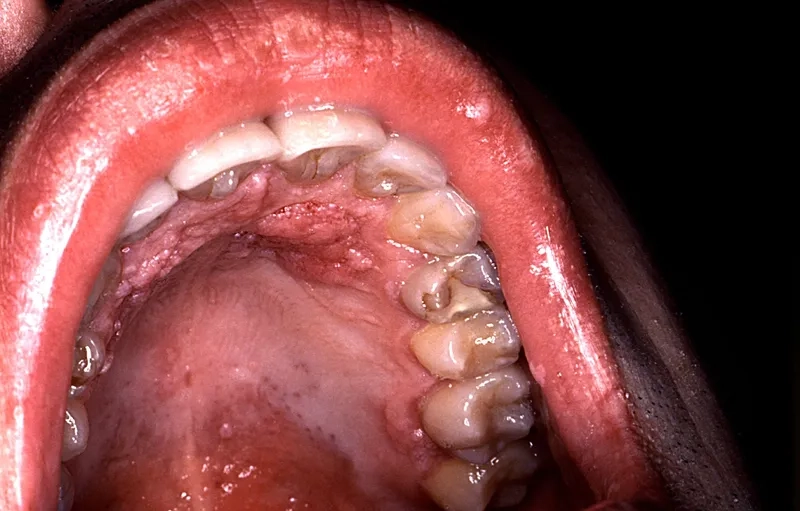

A clinical depiction of genital warts